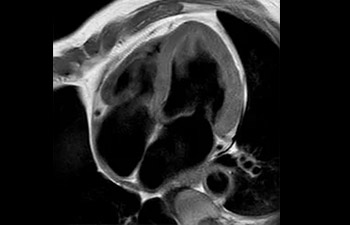

com Compressed SENSE

A equipe de IRM do Hospital Central Kurashiki incorporou o Compressed SENSE à maioria dos protocolos de exames do cérebro, coluna, abdômen e coração do seu Ingenia 1.5T, o que resultou em varreduras de IRM mais rápidas e de alta qualidade, um resultado apreciado por pacientes e pela equipe.